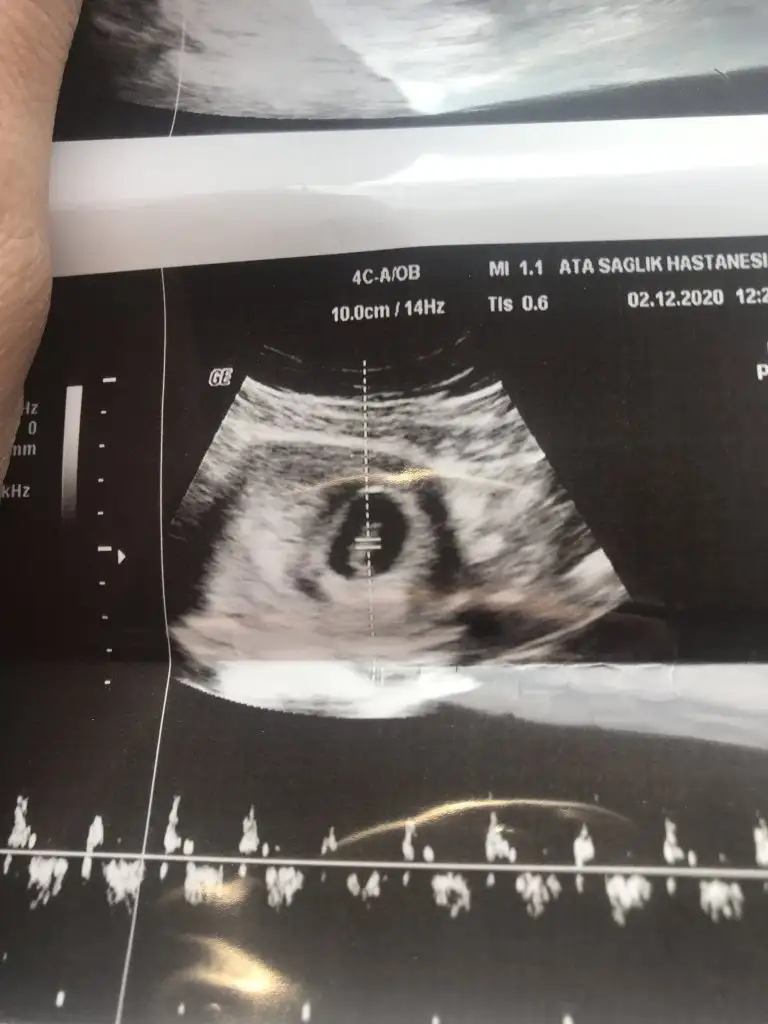

Kızlar 6+2 vajinal görüntü. Yalnız hastane ismi düzken ultrason görüntüsü ters görünüyor.

2. Son fotoda kağıdı ters çevirince ultrason görüntüsü düzeliyor. Öyle ki bebeğin başı belli oluyor. Yorumlarmısınız 😊